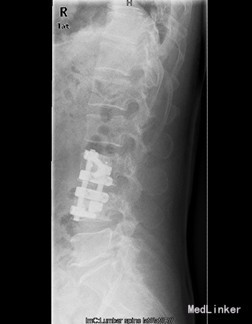

初步诊断:腰4椎体骨质破坏:结核?肿瘤? 诊疗计划:经前路腰4椎体部分切除,椎管减压,取自体髂骨植骨融合,Antares内固定术

术中见腰4椎体骨质破坏,其内可见空腔形成,周围骨质硬化,左侧椎旁椎体空腔内可见少量干酪样坏死组织,腰3、4椎间盘破坏、碎裂,部分组织突入椎管,压迫硬膜囊,取坏死组织术中冰冻切片示:肉芽肿性炎症伴坏死。